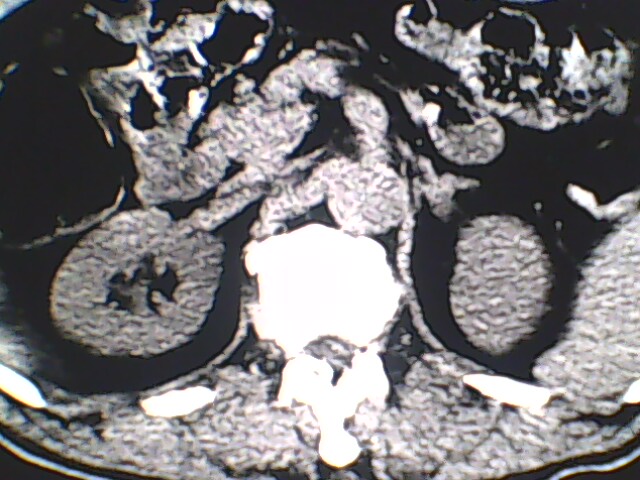

男,56岁,高血压,临床怀疑肾上腺问题,肝脏怎么那么高啊?能描述一下么?

右侧膈膨升,间位结肠,胸腰椎退行性骨关节病,右侧肾上腺可疑增生(图像颗粒太粗,窗太窄,不好看)。

支持 右侧膈膨升,间位结肠;胸腰椎退行性骨关节病;双侧肾上腺可疑增生。